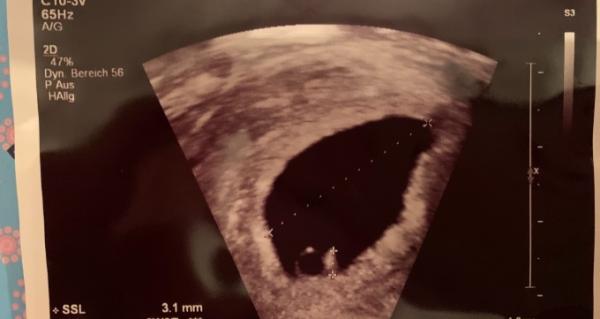

Hallöchen, bei mir hat’s 5+5 so ausgesehen

Und gestern hätte ich 7+5 sein sollen, wurde jedoch 2 Tage auf 7+3 zurückdatiert